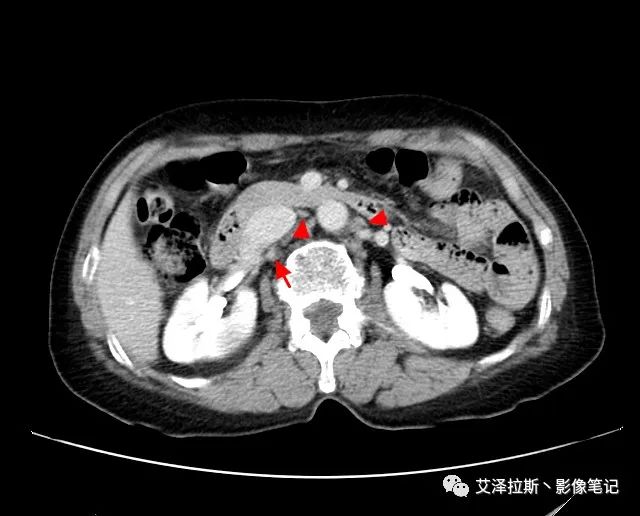

以下為累及的區域淋巴結,共計15個區域:

【影像所見】 胃竇部狹窄,胃壁環形增厚,小彎側見一巨大潰瘍,周圍伴“環堤征”,漿膜面不完整,胃周脂肪見網格狀條索影,病灶與肝臟左葉、胰腺鉤突脂肪間隙消失,增強掃描病灶明顯強化。引流區內約15個區域淋巴結受累。

【診斷意見】 胃竇部胃癌(T4N3期) 該病例腫塊突破漿膜層,與肝臟左葉、胰腺鉤突分界不清,脂肪界面消失,定為T4期; 受累及的淋巴結為15個區域,定為N3; 有無遠處轉移尚不明確,所以M期暫時無法確定。